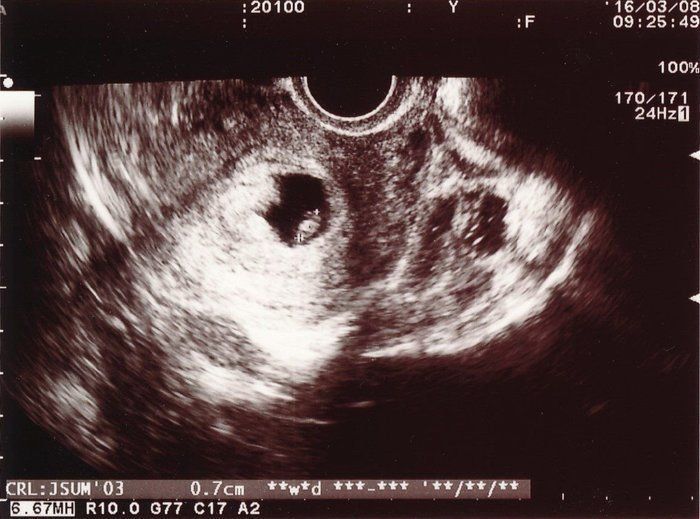

妊娠4週3日 以後妊娠5週0日まではGSは毎日1mmずつ大きくなります 妊娠5週目以降は、GSの成長が人によって異なります 排卵後 23日目 妊娠5週2日までにGS内に卵黄嚢(YS)が確認できます YSの大きさが5mm以上の場合、流産の可能性があります 排卵後 26日目数えかたも正確でないのですが、最終の生理は 11月19日開始でした! 排卵日は不明で、周期は某サイトで33日と算出されています また、某サイトで週数計算すると、私的には5週目かと思っていたのですが、4週3日でした! 私も胎嚢の大きさが心配です さて、当たり前ですが週4勤務ということは毎週必ず週3日が休みなわけです。 そうなると、 必然的に時間に余裕が生まれてきます。 なんせ、 今まで土日にやらねばできなかったことを水曜日の休みにすることができるんですからね。

妊娠4週 3 6日 のエコー写真 体験談

妊娠4週3日 4w3d の超音波 エコー 写真